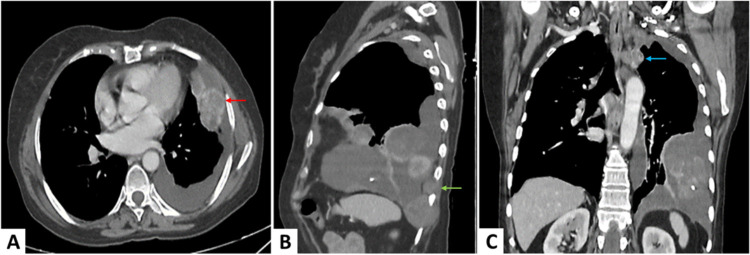

Low-grade fibromyxoid sarcoma (LGFMS) is a rare fibroblastic neoplasm with an indolent clinical course. It is a distinctive subclass of soft tissue sarcoma with metastasizing potential and sometimes a long interval between tumor presentation and metastasis. This case report describes a 60-year-old female with an unresectable pleural LGFMS initially misdiagnosed as malignant mesothelioma. Pleural LGFMS remains exceedingly rare, with only four prior cases reported. Given its histologically benign appearance, LGFMS poses diagnostic challenges and risks of local recurrence or metastasis. This case underscores the importance of accurate diagnosis using MUC4 and it explores endocrine therapy as a promising palliative option for unresectable LGFMS, contributing valuable insights into management strategies for this rare entity.